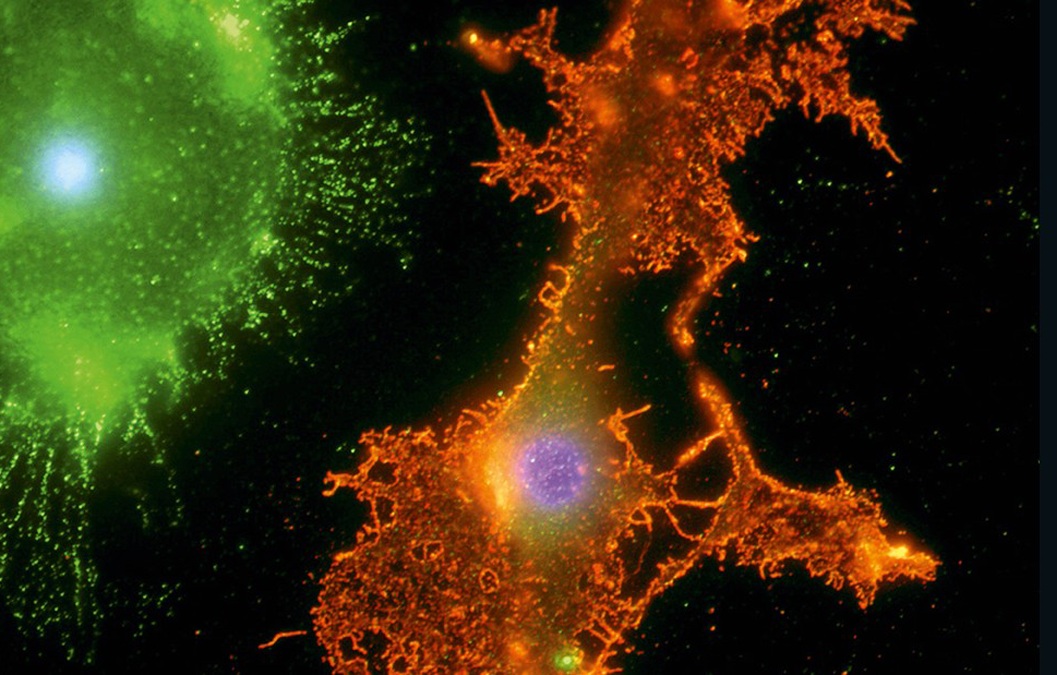

Computers are dry and nonbiological. The human brain is wet and biological. And it operates throughout every part of our body. Human consciousness—looking, talking, painting, playing ball, praying—is biological. The fact that our brains spill out onto the world in the expressive ways that they do should put us in some awe.

Used by permission.

Our beautiful, complex brains may or may not be the last frontier, but we have a way to go in understanding all that they are. They are the processors and interpreters of our humanity. And they break our hearts when they don't work right.

The above image of a human brain neuron was achieved with a SEM, or scanning electron microscope, which produces images using a focused beam of electrons. Neurons allow information to be received, interpreted, and relayed around the body. The long, thin structures that radiate outward from the cell body are called neurites, a general term for the process of nerve cells connecting to form a network. A neurite can be a dendrite, which receives the nerve impulses, or an axon, which transmits them.

Neurons form all of the information circuits in our brains, and they are always monitoring their activity levels. At each synapse, they process the chemical messages they receive so they can maintain a consistent level of synaptic activity and properly respond to the signaling around them.

Neurons constantly alter their DNA levels to maintain this balance and in the process mutations and slight excisions (cuts) can occur. Researchers who study mental illness and other brain dysfunctions are now working on whether some brain disorders occur because certain neurons lose their flexibility or are altered after a slight DNA excision.